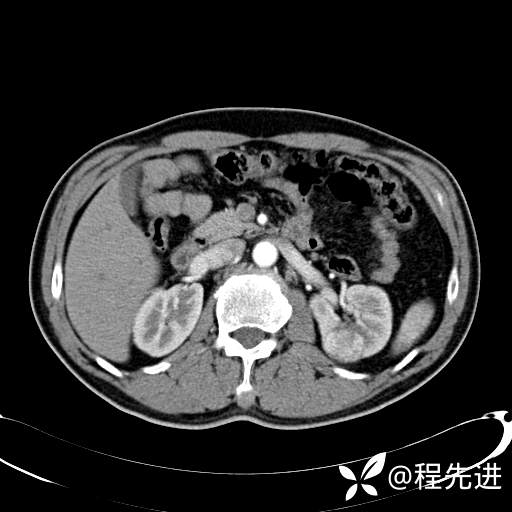

患者性别:男

患者年龄:65岁

简要病史:腰痛2月,体检发现左肾占位5天

髓质期: